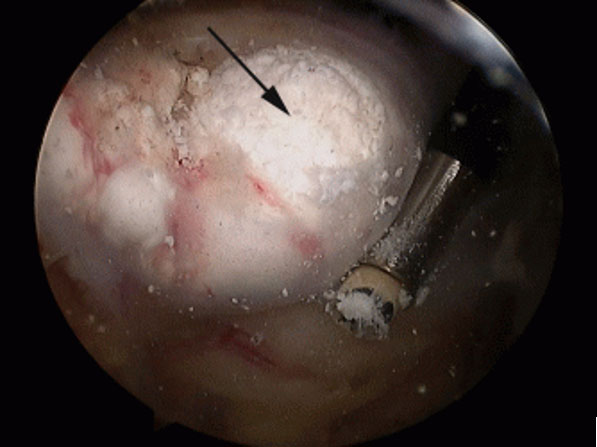

Artroszkópos kalcium depozit kiürítés

A váll meszes íngyulladásának (calcificáló tendinitis) létezik műtéti megoldása, amennyiben a konzervatív kezelés nem hoz tartós eredményt. A műtét lényege, hogy rotátorköpeny ínainak állományában felrakódott mész csomót sebészi úton kiürítjük. Az artroszkópos technikával végzett beavatkozás során rotátorköpeny külső rétegét szétválasztjuk és az alatta levő meszes ’fészeket’ alaposan kiürítjük. Előfordul, hogy az alapos mész eltávolítás érdekében az ínon nagyobb nyitást kell végezni. Ilyenkor az íngyógyulás érdekében a köpeny folytonosságát helyre kell állítani, ami a teljes felépülési időt megnyújthatja. Ezt a beavatkozást általában kiegészítjük fentiekben részletezett subacromiális decompresszióval. Rehabilitáció hozzávetőlegesen 3 hónapot is igénybe vehet.